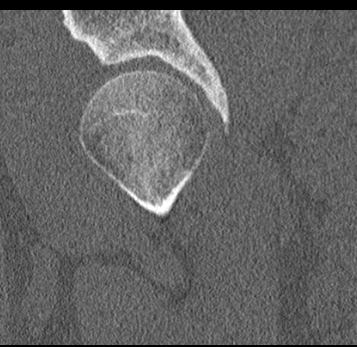

КТ относится к лучевым методам исследования, то есть предусматривает использование рентгеновского излучения, которое хорошо поглощается костной тканью. В результате сканирования и последующей цифровой обработки полученных данных получаются подробные снимки в различных плоскостях, а также трехмерные изображения тазобедренных суставов, позволяющие оценить пространственное расположение суставных поверхностей, внутрисуставных структур и окружающих тканей.

Снимки высокого разрешения позволяют выявить минимальные изменения в костных структурах и окружающих тканях. Мультиспиральная КТ может применяться в экстренных ситуациях для диагностики травматических повреждений тазобедренных суставов, в частности, при переломах шейки бедра. Кроме того, исследование незаменимо при планировании оперативного вмешательства, а также в послеоперационном периоде для оценки успешности проведенной операции и для отслеживания процесса восстановления.

Что показывает КТ тазобедренного сустава

- повреждения костной ткани (перелом головки, шейки бедра, вертлужной впадины);